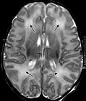

0 Σχολίασαν Αναρτήθηκε από τον Dr D. Kountouris at 12:51 π.μ.Ερεθίζοντας αισθητήρια όργανα και καταγράφοντας αντιδράσεις από το φλοιό του εγκεφάλου μπορούμε να εντοπίσουμε δυσλειτουργίες στη διαδρομή του εγκεφαλικού ερεθισμού και να καταγράψουμε τις ανωμαλίες που παρουσιάζονται. Με αυτό τον τρόπο έχουμε τη δυνατότητα να καταγράψουμε έγκαιρα κάθε απόκλιση από το φυσιολογικό. Σε ότι αφορά τα προκλητά δυναμικά που παρουσιάζονται στον αρχικό χρόνο, εξετάζουμε ανατομικές δυσλειτουργίες, ενώ σε αυτά που εμφανίζονται σε μακρύτερο χρονικό διάστημα καταγράφουμε πνευματικές ή ψυχικές λειτουργίες.

Με αυτό τον τρόπο στην καταγραφή των προκλητών δυναμικών σε όλες σχεδόν τις νευροψυχιατρικές διαταραχές έχουμε τη δυνατότητα της αξιολόγησης σε πραγματικό χρόνο όλων εκείνων των εγκεφαλικών διεργασιών που πραγματοποιούνται για την εκτέλεση των γνωστικών λειτουργιών. Δηλαδή, έχουμε έναν τρόπο με τον οποίο μπορούμε πλέον και απεικονιστικά να εκτιμήσουμε νευρωνικές διαταραχές.

ΕΓΚΕΦΑΛΟΣ: ΠΡΟΚΛΗΤΑ ΔΥΝΑΜΙΚΑ: ΈΛΕΓΧΟΣ ΑΙΣΘΗΤΗΡΙΩΝ ΟΡΓΑΝΩΝ

0 Σχολίασαν Αναρτήθηκε από τον Dr D. Kountouris at 11:59 μ.μ.Τα προκλητά δυναμικά έφεραν στον τομέα αυτό μια αληθινή επανάσταση, λόγω του μεγαλοφυούς της σύλληψης τους και του απλού της καταγραφής τους. Έτσι λοιπόν, πολύ απλοϊκά, ερεθίζοντας ένα αισθητήριο όργανο π.χ. δέρμα ή μάτι, μπορούμε να καταγράψουμε από το αντίθετο κέντρο του εγκεφάλου, πέρα από ένα δυναμικό, λόγω του ερεθισμού, και τον λανθάνοντα χρόνο που μεσολαβεί μεταξύ ερεθισμού και καταγραφής. Έτσι λοιπόν, έχουμε ταυτόχρονα δυο παραμέτρους προς μέτρηση που αποτελούν και σημείο αναφοράς για μια σύγκριση μεταξύ παθολογικών και φυσιολογικών καταστάσεων.